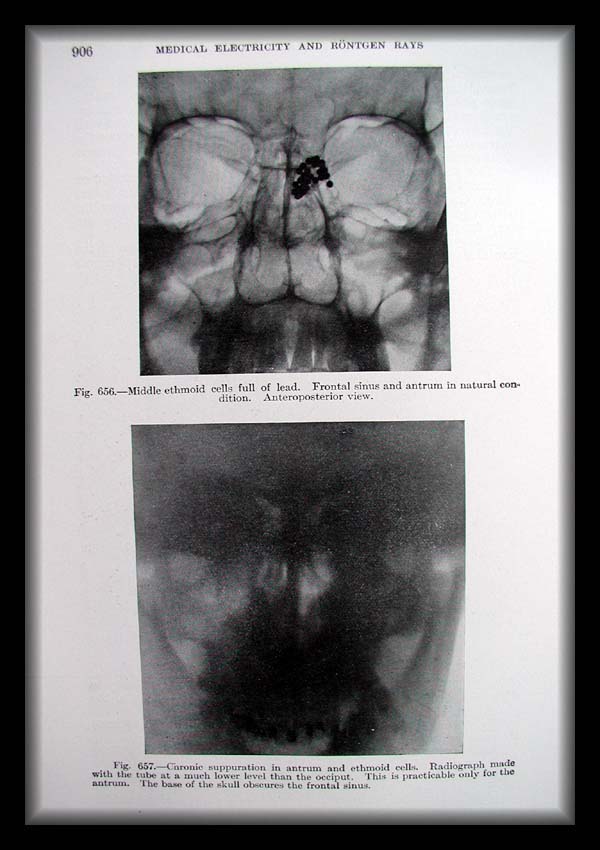

Page0906